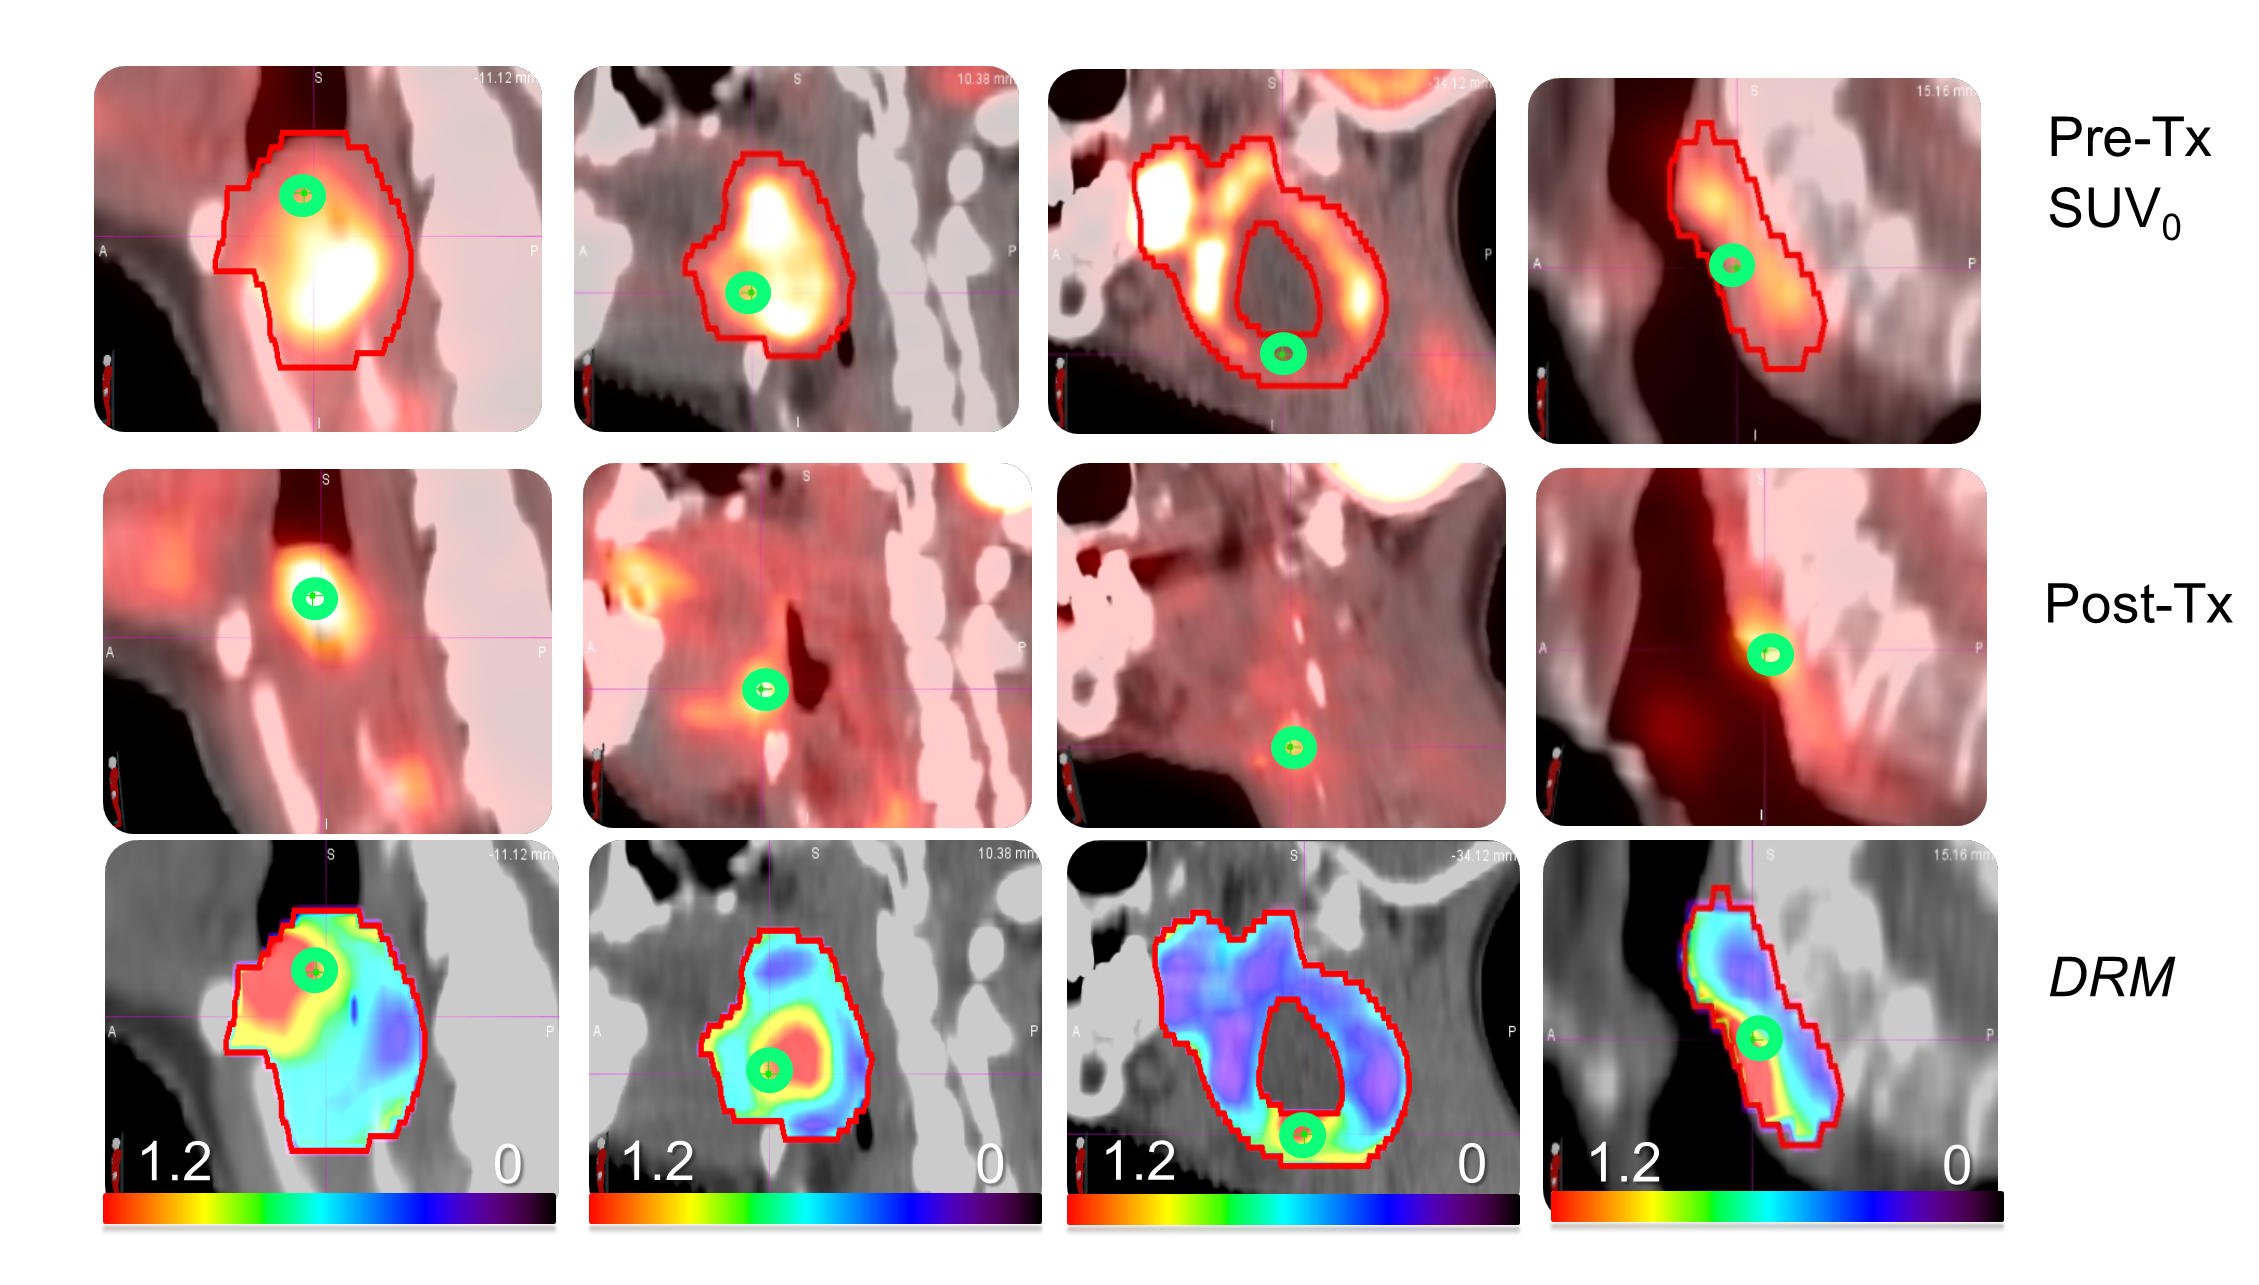

Figure 1. The vertical columns show the pre-treatment FDG-PET images (upper), post-treatment FDG-PET images at local recurrence (center) and DRM images during treatment after 40 Gy (lower) for the four patients that failed treatment locally. The green circle represents the same tumor voxels in each image.

We have previously reported the development of a tumor dose sensitivity or response matrix (DRM) [5,[6] that was constructed at the positron emission tomography (PET) image voxel-level using multiple fluorodeoxyglucose (FDG)-PET/computed tomography (CT) images obtained before and during the early weeks of chemoradiation for HNSCC. The tumor voxel dose sensitivity, DRM, was derived based on the first order reaction law of cell killing from the linear regression of logarithmic ratio of tumor metabolic activity with treatment and is unique for each voxel. The tumor dose sensitivity matrix is highly individualized and has a strong capability to identify radioresistant tumor voxels during the early course of radiotherapy. Combining with the pre-treatment baseline PET standardized uptake vale (SUV), it results in a high capability to predict local tumor failure (Figure 1). Importantly, a tumor voxel control probability (TVCP) lookup table was created using the maximum likelihood estimation on these key tumor voxel parameters, the tumor voxel DRM and baseline SUV, which can be used as the objective function for adaptive dose painting by numbers (DPbN)-based inverse planning optimization [5,6]. In addition, considering the efficacy of hypofractionation for resistant tumor cells, early identification of distinct subpopulations derived from the intratumoral dose response could also be utilized to design dose fractionation painting by numbers (DFPbN) adaptively.

Our data is consistent with heterogeneity and plasticity within the stem cell compartment. Those tumors that failed did not show any clear patterns on tumor voxel dose sensitivity distribution. Resistant tumor voxels were not correlated to the pre-treatment SUV and not at any special location within tumor. Based on the post-treatment PET-CT images, the recurrent tumor voxels were among the resistant voxels. However, large numbers of tumor voxels for these 4 failures were within the controlled region and some of them were very sensitive to the treatment dose. For these tumor voxels, a treatment dose, even lower than the standard prescription dose of 70Gy, could be appropriate. This highlights the variation in radiosensitivity and offers the possibility to escalate and de-escalate treatment plans based on individual voxel sensitivity.